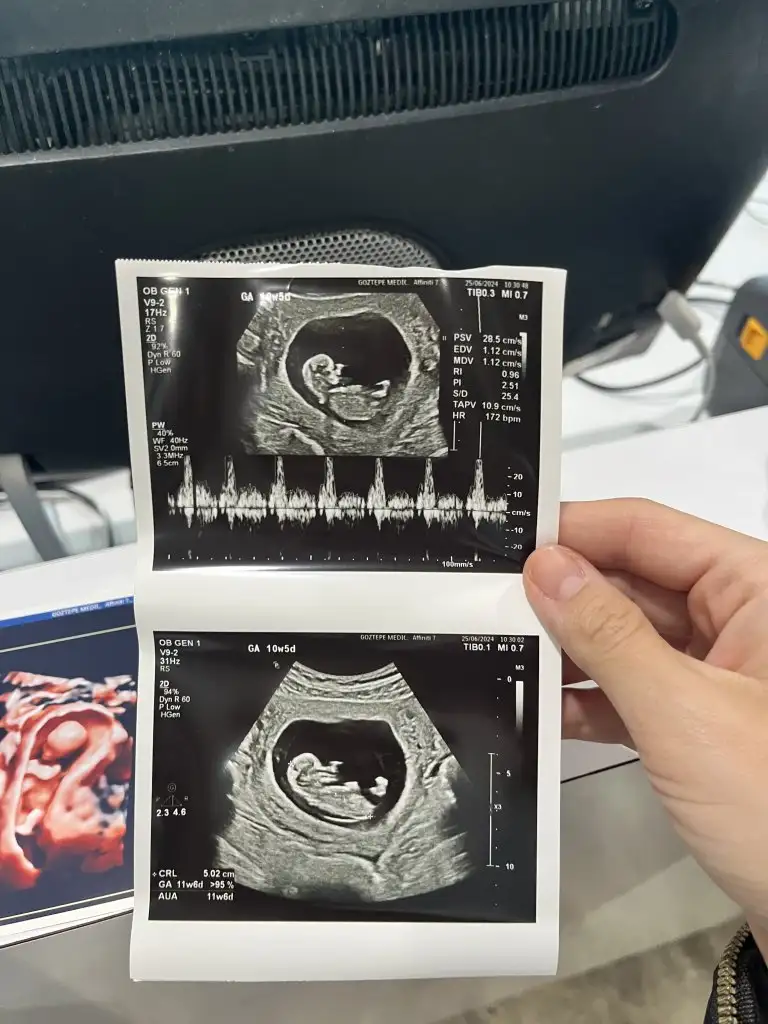

Ayy maşallahKızlar bugün doktor kontrolum vardı bizim fasulyeyi ilk defa eli ayağı varken gördük çok heycanlıydı 10hafta 5 günlüğüm ama boyu 11 hafta 6 günlük gibiymiş bi hafta önden gidiyoruz bende cinsiyet tahminleri alayım![]()

Bence erkek öyle hissettimKızlar bugün doktor kontrolum vardı bizim fasulyeyi ilk defa eli ayağı varken gördük çok heycanlıydı 10hafta 5 günlüğüm ama boyu 11 hafta 6 günlük gibiymiş bi hafta önden gidiyoruz bende cinsiyet tahminleri alayım![]()

HarikaKızlar bugün doktor kontrolum vardı bizim fasulyeyi ilk defa eli ayağı varken gördük çok heycanlıydı 10hafta 5 günlüğüm ama boyu 11 hafta 6 günlük gibiymiş bi hafta önden gidiyoruz bende cinsiyet tahminleri alayım![]()